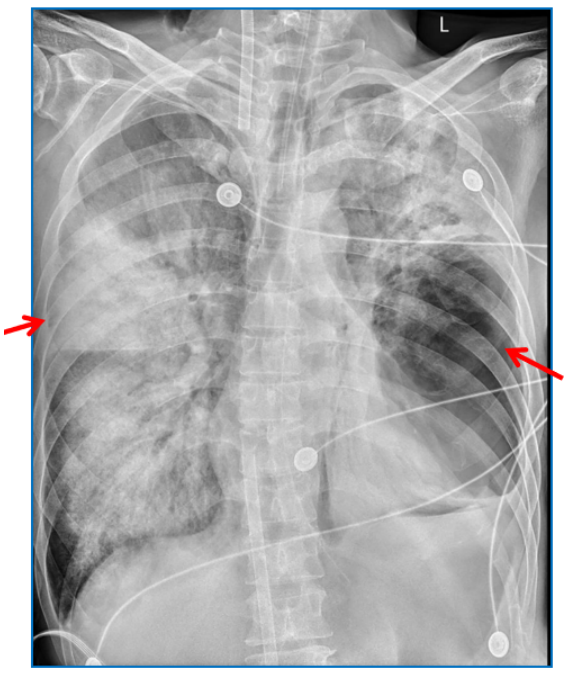

影像学:2023年12月27日床旁胸片示:右肺和左肺上叶透亮度明显下降,大片实变和渗出;左肺下叶有空泡影(图1)。ECMO上机第3天复查胸部CT示双肺多发渗出和实变,左肺下叶有脓腔形成(图2)

图1  患者入院当天胸部X线片